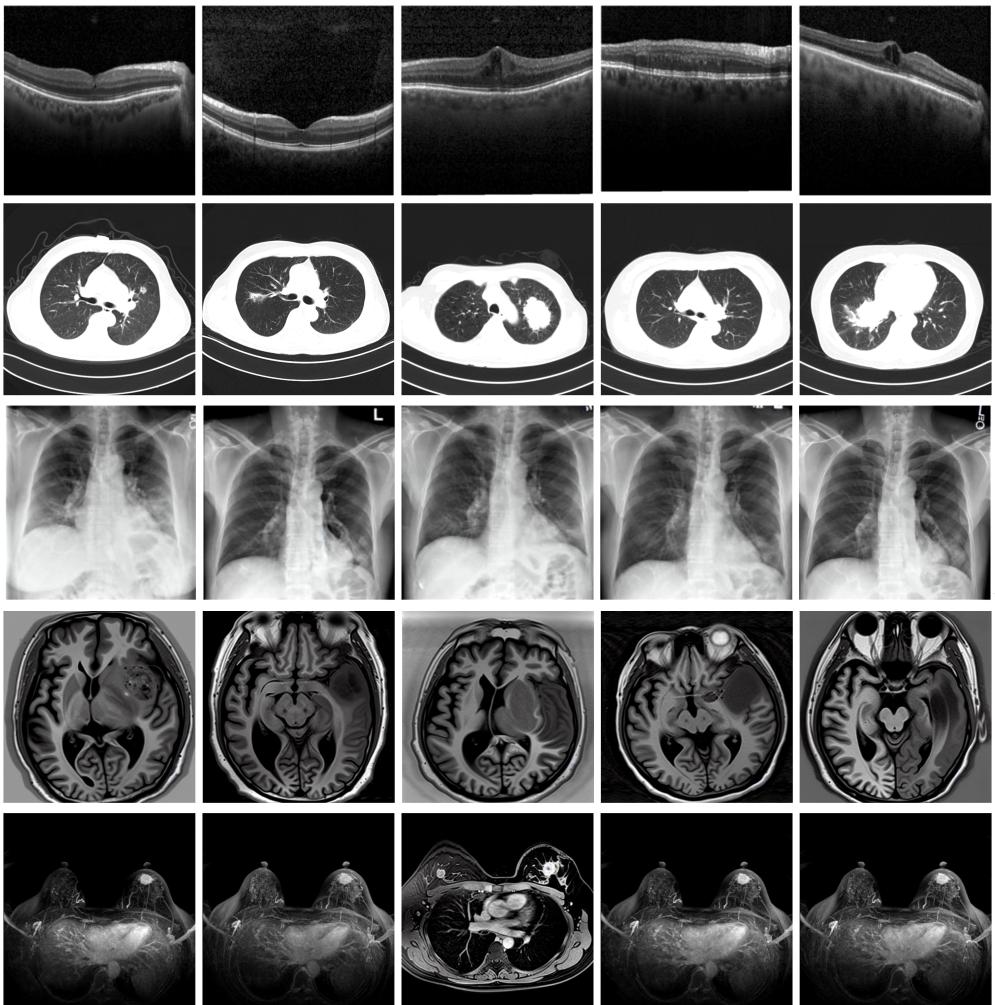

圖為由MINIM生成的高質量醫(yī)學合成圖像(受訪者供圖)

“目前公開的醫(yī)學影像數(shù)據(jù)非常有限,我們建立的生成式模型有望解決訓練數(shù)據(jù)不夠的問題?!北本┐髮W未來技術學院助理研究員王勁卓說,研究團隊利用多種器官在CT、X光、磁共振等不同成像方式下的高質量影像文本配對數(shù)據(jù)進行訓練,最終生成海量的醫(yī)學合成影像,其在圖像特征、細節(jié)呈現(xiàn)等多方面都與真實醫(yī)學圖像高度一致。

實驗結果顯示,MINIM生成的合成數(shù)據(jù)在醫(yī)生主觀評測指標和多項客觀檢驗標準方面達國際領先水平,在臨床應用中具有重要參考價值。在真實數(shù)據(jù)基礎上,使用20倍合成數(shù)據(jù)在眼科、胸科、腦科和乳腺科的多個醫(yī)學任務準確率平均可提升12%至17%。